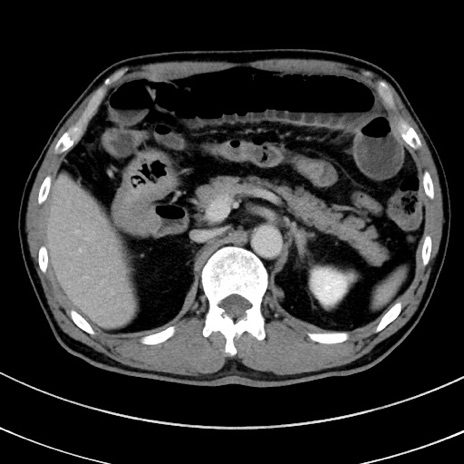

症例8(横断像)

【症例】 60歳代男性

【主訴】 黒色吐物

【現病歴】 4日前から嘔気自覚、2日前の朝食後にも嘔気あり、自分で手で嘔吐反射起こし嘔吐したところ血が混ざっていたため受診。

【既往歴】 5年前汎発性腹膜炎を伴う急性虫垂炎で手術、高血圧、前立腺肥大症、高脂血症

【身体所見】 腹部正中に手術癩痕あり 腹部平坦・軟圧痛なし膨満感あり

【データ】WBC 8400、CRP 4.54